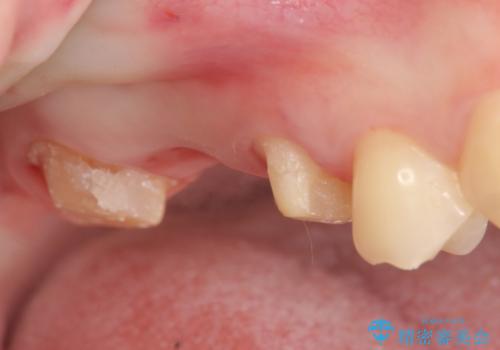

右上6番目の歯は虫歯が深く、保存が難しかったため抜歯しました。

その後歯茎や骨の回復を待ち、オールセラミッククラウンのブリッジによる補綴を行いました。